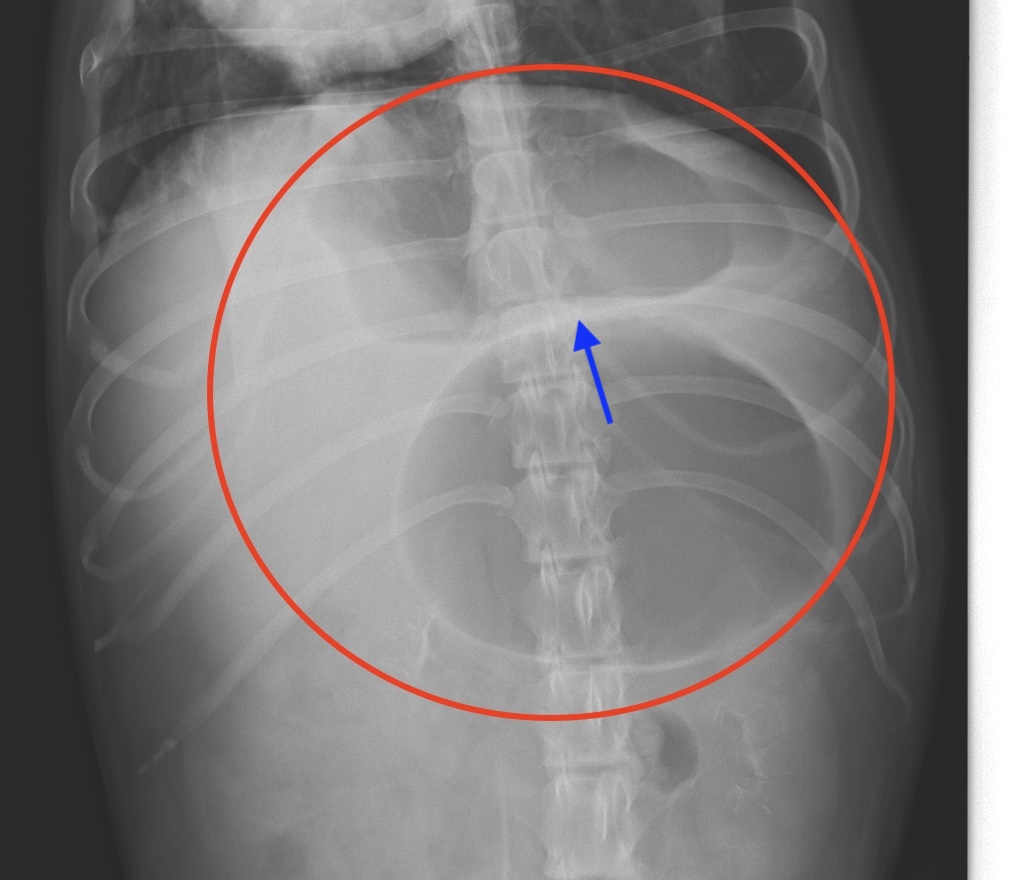

胃拡張胃捻転症候群のレントゲン画像(赤丸)

胃の部分に白いライン(青矢印)がみられるのが特徴です。